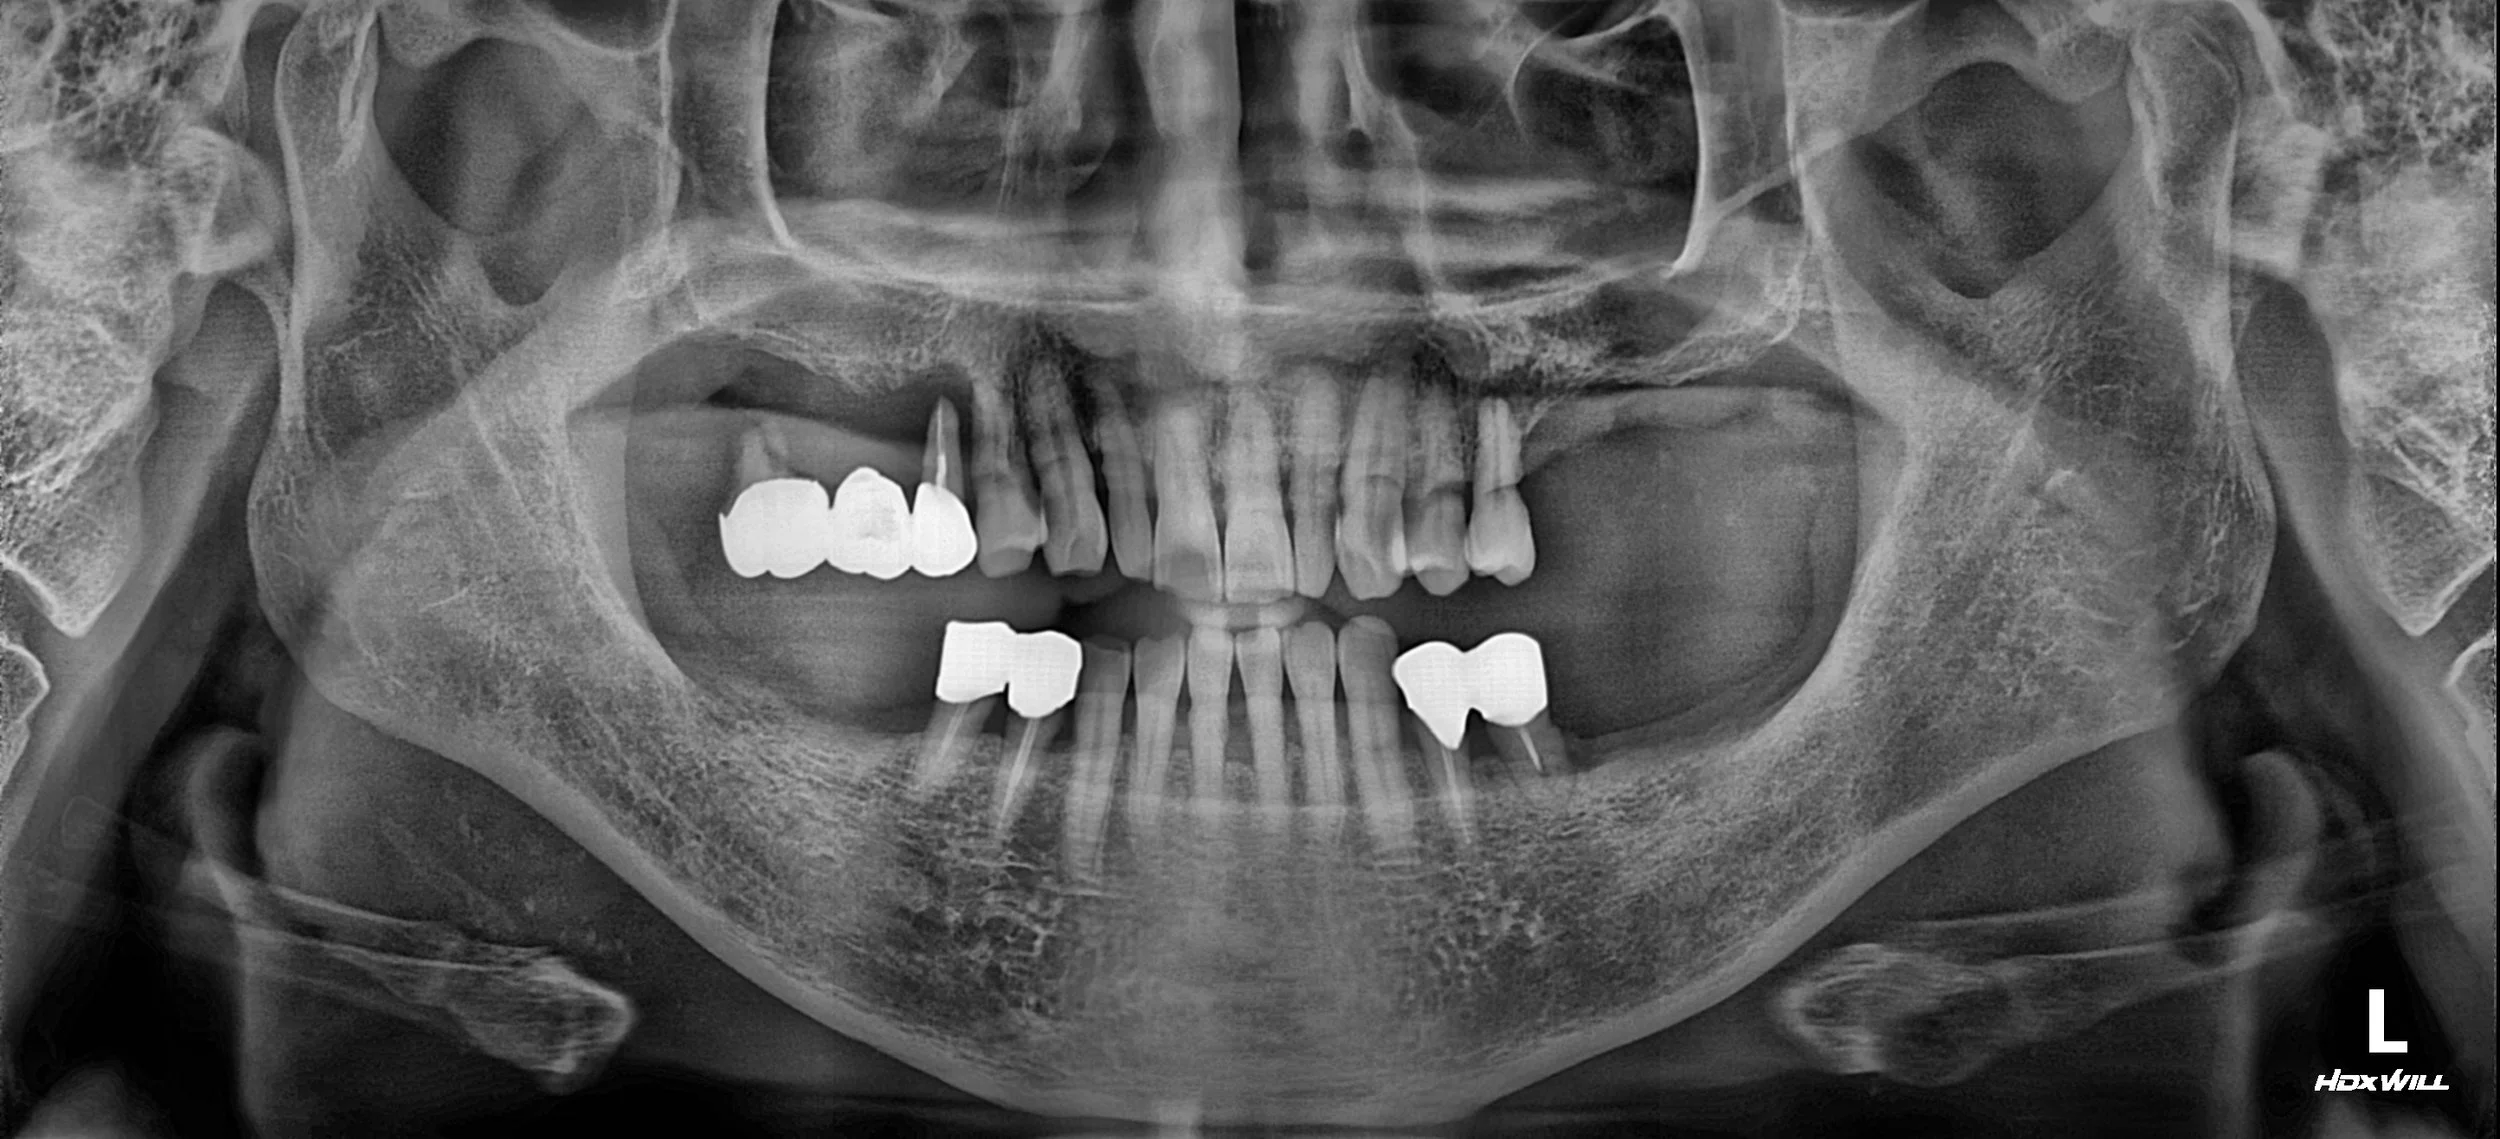

17. Reconstructing Class III Malocclusion: A Strategic Approach to VDO Elevation

Case Summary

A male patient in his 50s presented with a severely compromised dentition and a history of failed dental rehabilitation. Having previously received partial dentures that were too uncomfortable to use, the patient had neglected further treatment, leading to:

• Class III Malocclusion: A pronounced underbite exacerbated by posterior tooth loss.

• Mandibular Deviation: Abnormal jaw shifting during closure due to lack of stable occlusal stops.

• Insufficient Restorative Space: A collapsed Vertical Dimension of Occlusion (VDO) making fixed prosthetics challenging.

OPG - BEFORE